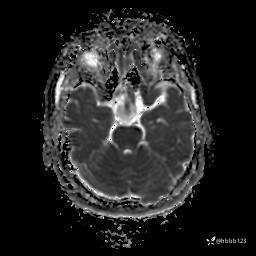

DWI:

ADC: